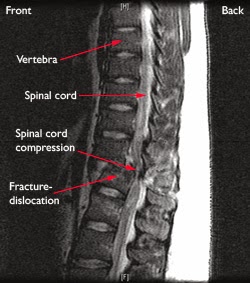

Fraktur - dislokasi . Ini adalah cedera yang tidak stabil yang melibatkan tulang dan / atau jaringan lunak di mana vertebra mungkin bergerak dari sebuah vertebra yang berdekatan (displaced ) . Cedera ini sering menyebabkan kompresi sumsum tulang belakang yang serius .

Perhatikan gangguan sumsum tulang belakang .

A CT scan diambil dari sisi fraktur - dislokasi pada tulang belakang dada .

Tes pencitraan . Setelah pemeriksaan fisik , evaluasi radiologis diperlukan . Tergantung pada sejauh mana cedera , ini mungkin termasuk x-ray, computed tomography ( CT ) scan , dan magnetic resonance imaging ( MRI ) scan dari beberapa daerah , termasuk dada dan lumbar tulang belakang .